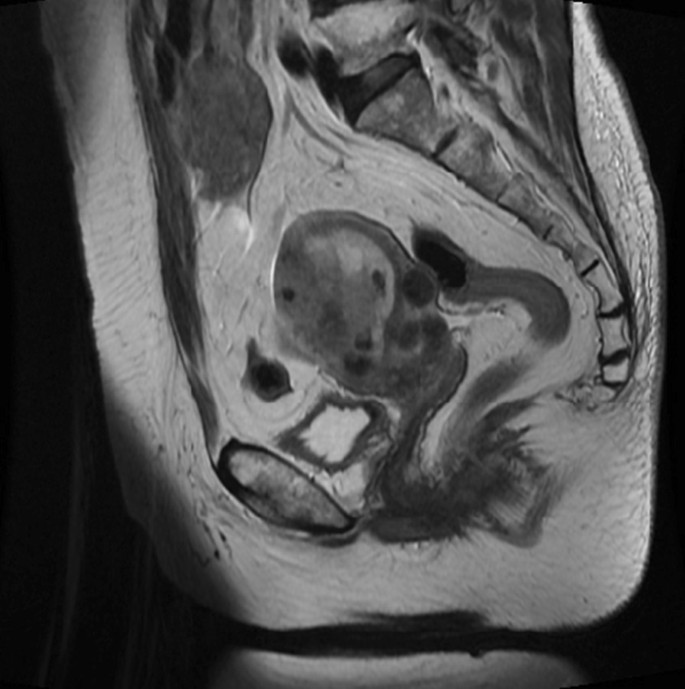

A 72-year-old Japanese woman on medications for hypertension, obesity, and diabetes mellitus, was referred to our hospital with abnormal uterine bleeding. She was previously diagnosed with abnormal endometrial cytology at a previous clinic and visited our hospital for further examination and treatment. Endometrial biopsy revealed an adenocarcinoma (G2), while pelvic magnetic resonance imaging revealed a lesion mass of size 60 × 66 × 53 mm in the right side of the uterus (Fig. 1), which was suspected to invade the serosal side. An enlarged lymph node measuring 18 mm was also found in the lymph node clusters in the right internal iliac artery and the obturator lymph node. Therefore, hysterectomy, bilateral adnexectomy, pelvic lymph node dissection, and para-aortic lymph node dissection were performed. A pathological examination using surgical specimen revealed endometrial serous carcinoma (Fig. 2). Finally, she was diagnosed with stage III C2 endometrial cancer.